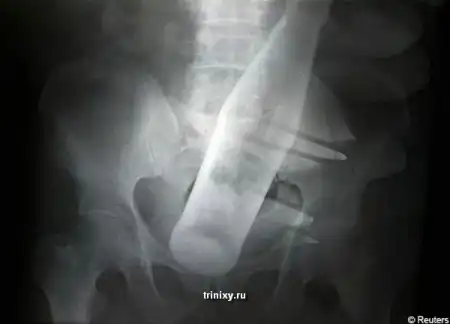

История такова. Грабители хотели украсть буйволов этого пожилого человека. Но он оказал сопротивление и тогда бандиты решили силой забрать скот у него. Чтобы старик согласился в ход пошла стеклянная бутылка из под Pepsi. Она была полностью засунута в задний проход. Естественно бедолага не смог самостоятельно избавиться от инородного тела, находящегося у него внутри и ему пришлось обратиться в больницу. Хирург, обследовавший его , увидев снимок потерял дар речи. Потерпевшему пришлось пройти серьезный курс лечения.